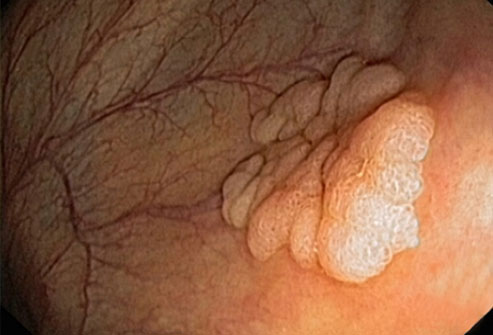

结直肠癌

大多数结肠癌是大肠内壁生长的息肉发展而来的。息肉可能是也可能不是癌细胞。如果息肉属于癌细胞,那么癌细胞可能会扩散到身体的其他部位。在息肉癌变前就将其移除,可以完全预防结肠癌。

结直肠癌筛查

结肠镜检查是一种常见的结直肠癌的筛检方法。医生会使用结肠镜进行检查。如果发现息肉,医生可能在检查过程中将其移除。另一种测试是更灵活的乙状结肠镜检查,这种检查只会检查结肠下部。如果你的风险水平属于平均状态,筛查通常从50岁开始进行。